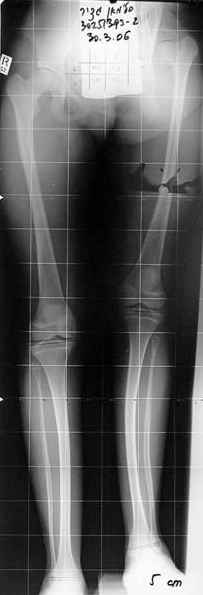

Devushka predstavlennaya na snimke nachala s LLD 9 cm, valgus deformation of the tibia, huge Trendelenburg( vidno na snimke).

Seichas : no LLD ,no Trendelenburg, reasonable hip motion.A samoe glavnoe ei ne predstoit kaghdye 10-15 let delat revision THR.